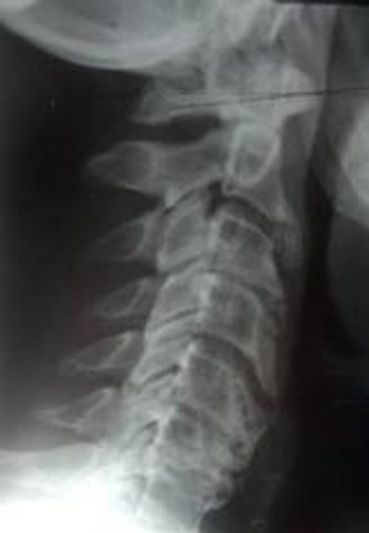

- Atlas Orthogonal/Spine

- Neck Trauma/Whiplash

- Spinal Disc Disorders

- Neck/Head Injury & Laser